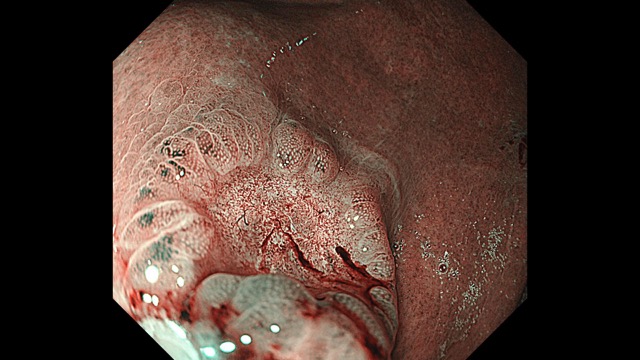

胃003